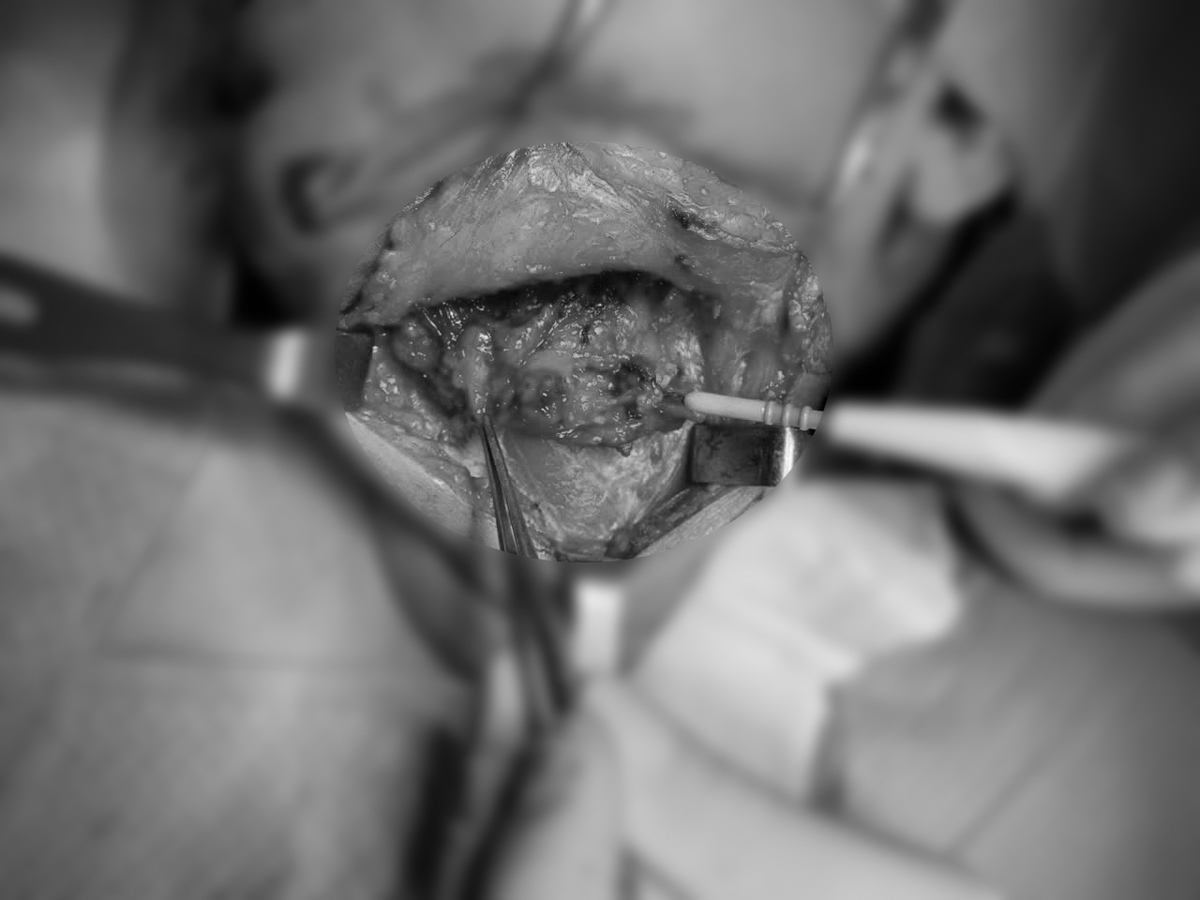

Ê-kíp bác sĩ thực hiện ca phẫu thuật kéo dài hơn 5 giờ đồng hồ loại bỏ khối u

Khối u xoang dần lộ diện sau quá trình bóc tách

Ê-kíp bác sĩ thống nhất tiến hành ca phẫu thuật phức tạp gồm 3 giai đoạn gồm: nạo vét hạch cổ, loại bỏ khối u và tái tạo vùng mặt.

Trải qua gần 5 giờ phẫu thuật, khối u được loại bỏ hoàn toàn, các vùng bị xâm lấn được tái tạo thành công. Nữ bệnh nhân sau mổ có sức khỏe ổn định, không xảy ra các biến chứng nguy hiểm và xuất viện chỉ sau 1 tuần.